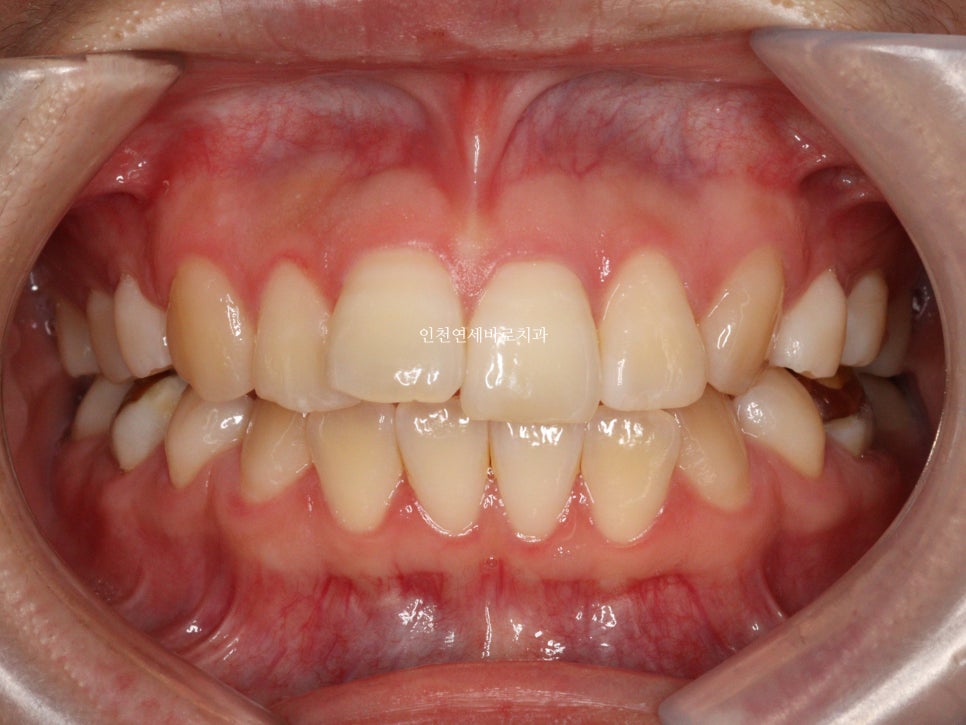

그리고 치료가 마무리 된 후의 모습입니다.

부분교정으로 앞니만 철사를 붙여서도 비슷한 효과를 볼 수 있었을지 모릅니다.

하지만 치아의 삭제가 많은 양 동반되지 않았다면 앞니가 분명 뻗쳐나왔을것입니다.

하지만 인비절라인은 전체교정에 준하는

치아와 주변조직에 무리가 되지 않는 범위에서의 확장을 만들어낼 수 있어

앞니의 뻗침을 최소화 할 수 있는 장점이 있습니다.

위 환자분의 재교정 치료기간은 약 7개월입니다.